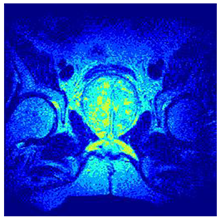

| Image | nt = 3 | nt = 4 | nt = 5 | nt = 8 |

|---|---|---|---|---|

| 1 | ![]() | ![]() | ![]() | ![]() |

| 2 | ![]() | ![]() | ![]() | ![]() |

| 3 | ![]() | ![]() | ![]() | ![]() |

| 4 | ![]() | ![]() | ![]() | ![]() |

| 5 | ![]() | ![]() | ![]() | ![]() |

| 6 | ![]() | ![]() | ![]() | ![]() |

| 7 | ![]() | ![]() | ![]() | ![]() |

| 8 | ![]() | ![]() | ![]() | ![]() |

| 9 | ![]() | ![]() | ![]() | ![]() |

| 10 | ![]() | ![]() | ![]() | ![]() |

| 11 | ![]() | ![]() | ![]() | ![]() |